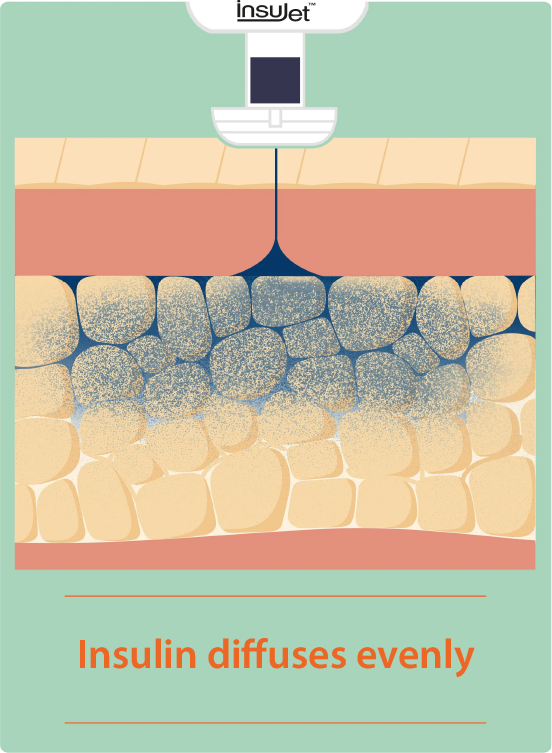

Traditional injection versus InsuJet™

Faster and effective absorption

- Optimized peak action

- Improved glycemic control

How does it work?

Applied to the skin, InsuJet™ delivers insulin in a thin jet injection that easily penetrates the skin, ensuring optimal distribution into the subcutaneous tissue.